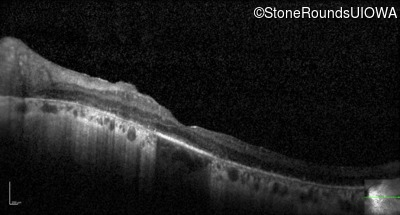

Optical Coherence Tomography - Right - 20/80

Exemplar / OCT Stack